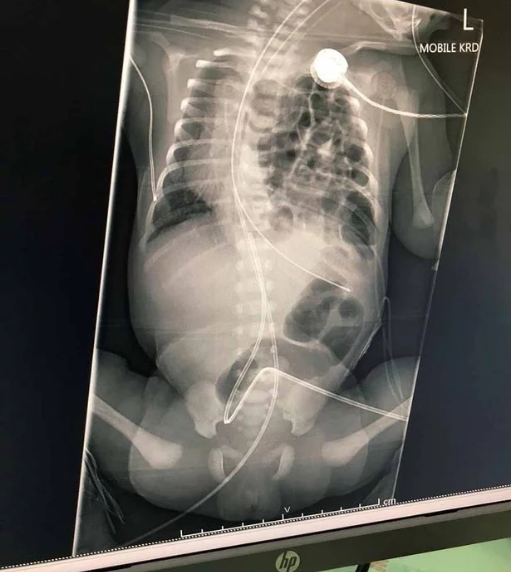

Ultrasound scan a year later revealed she actually had uterus didelphys, where a woman is born with two uteruses, two cervixes and, in her case, two vaginas.

According to the World Health Organisation, the condition affects around one in 3,000 women and occurs when the uterus fails to fuse properly during development in the womb.